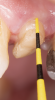

Fig 4. An adequate collar effect of 2 mm of sound tooth structure would provide an anti-rotational feature for the stability of the crown.

Figure 4

Fig 5. Buccal view of optimal ferrule effect with a healthy biological framework.

Figure 5